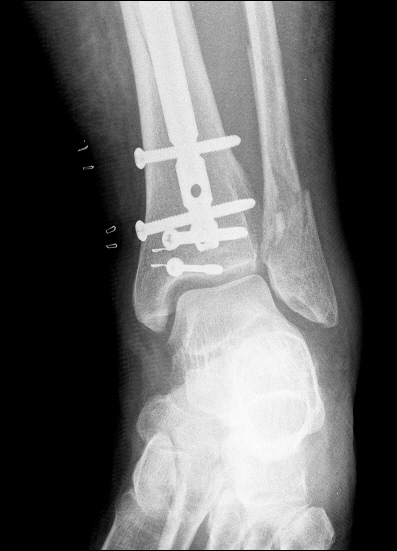

So onto the medical pics.

Dressing change before we head home